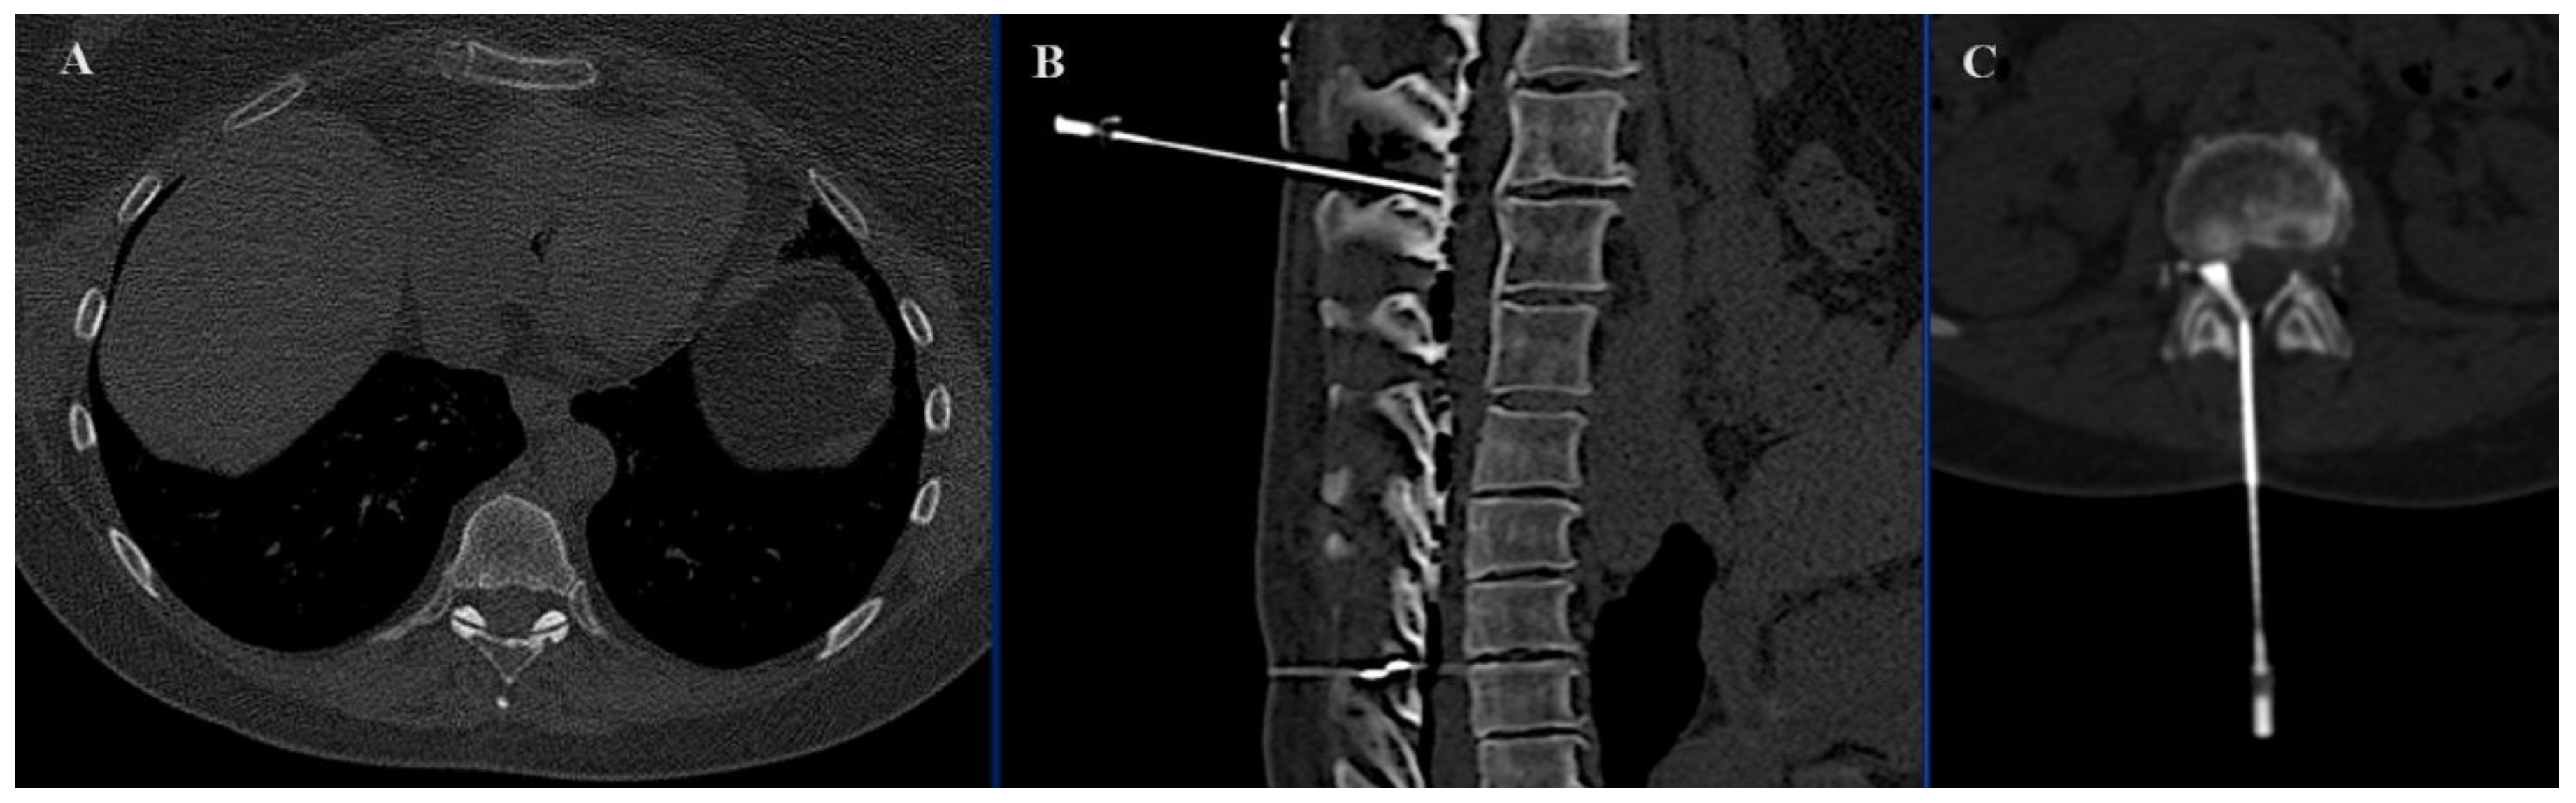

The findings of this study provide compelling evidence for the efficacy of the SIRIO navigation system in interventional procedures for vertebral RFA with neuroprotection, particularly in the treatment of primary and metastatic bone tumors. Our comprehensive analysis demonstrated significant improvements in procedural efficacy and patient outcomes when the SIRIO system was utilized. SIRIO-assisted neuroprotection is associated with a significant reduction in both dose-length product (DLP) and procedural time. The average DLP was significantly lower in the SIRIO group (307.42 mGycm) compared to the non-SIRIO group (460.31 mGycm). Reducing radiation exposure to patients is clinically relevant, as it minimizes potential risks associated with radiation, in line with existing literature highlighting the importance of reducing radiation doses in interventional radiology [6]. According to many studies, the majority of the radiation dose is contributed by the preliminary planning CT [8,9,10], and it is precisely at this stage that the navigation system facilitates the procedure. This data correlates with the procedural time, which was significantly shorter in the SIRIO-assisted group, with an average of 13.48 min compared to 32.26 min in the unassisted group. The navigation system helped to identify the most direct and shortest path of the needle to reach the epidural space (Figure 7), also making the procedure quicker. This evidence is significant, as shorter procedural times can reduce the risk of complications and improve overall patient performance in clinical settings [11]. The efficacy improvements observed with the use of the SIRIO navigation system highlight its potential to improve workflow and optimize resource utilization in interventional oncology.

Figure 7. Axial (A) image demonstrating the presence of an osteoid osteoma located in adjacency to the inferior articular facet of D9. Axial (B) image demonstrating correct needle positioning and CO2 epidural dissection.